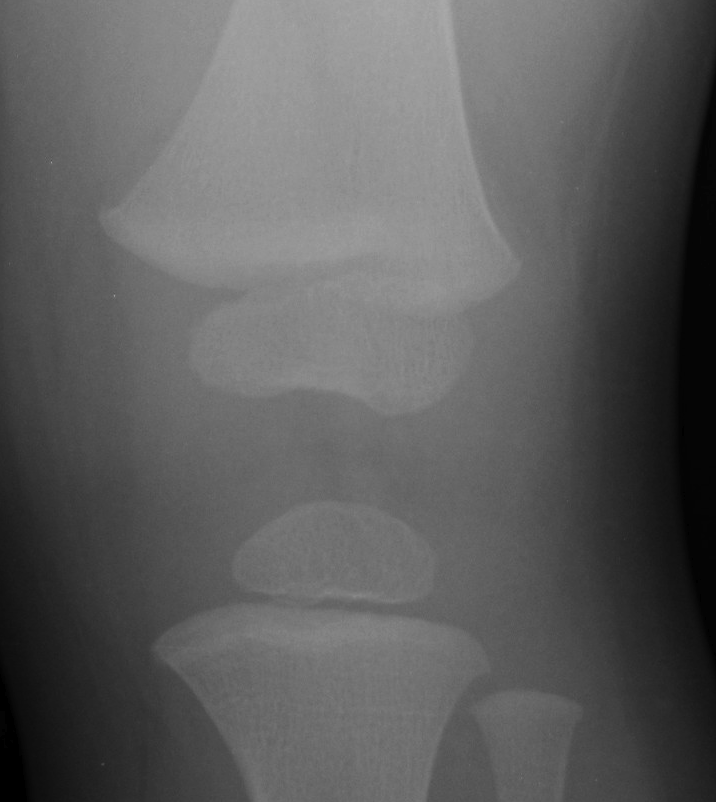

18 month old boy brought in by his mother after falling down 3-4 stairs yesterday afternoon, and has been limping since.

What is the injury and what is it associated with?